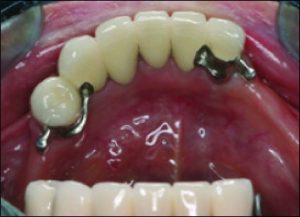

The use of direct retainers on isolated abutment teeth in distal extension PRD cases usually accelerates the destruction of the periodontium, leading to tooth loss. For this reason, it is recommended to place rests on isolated teeth and not to use direct retainers. Another option is restoration of the modification space with a fixed partial denture and splinting of the teeth (Figures 10-15).